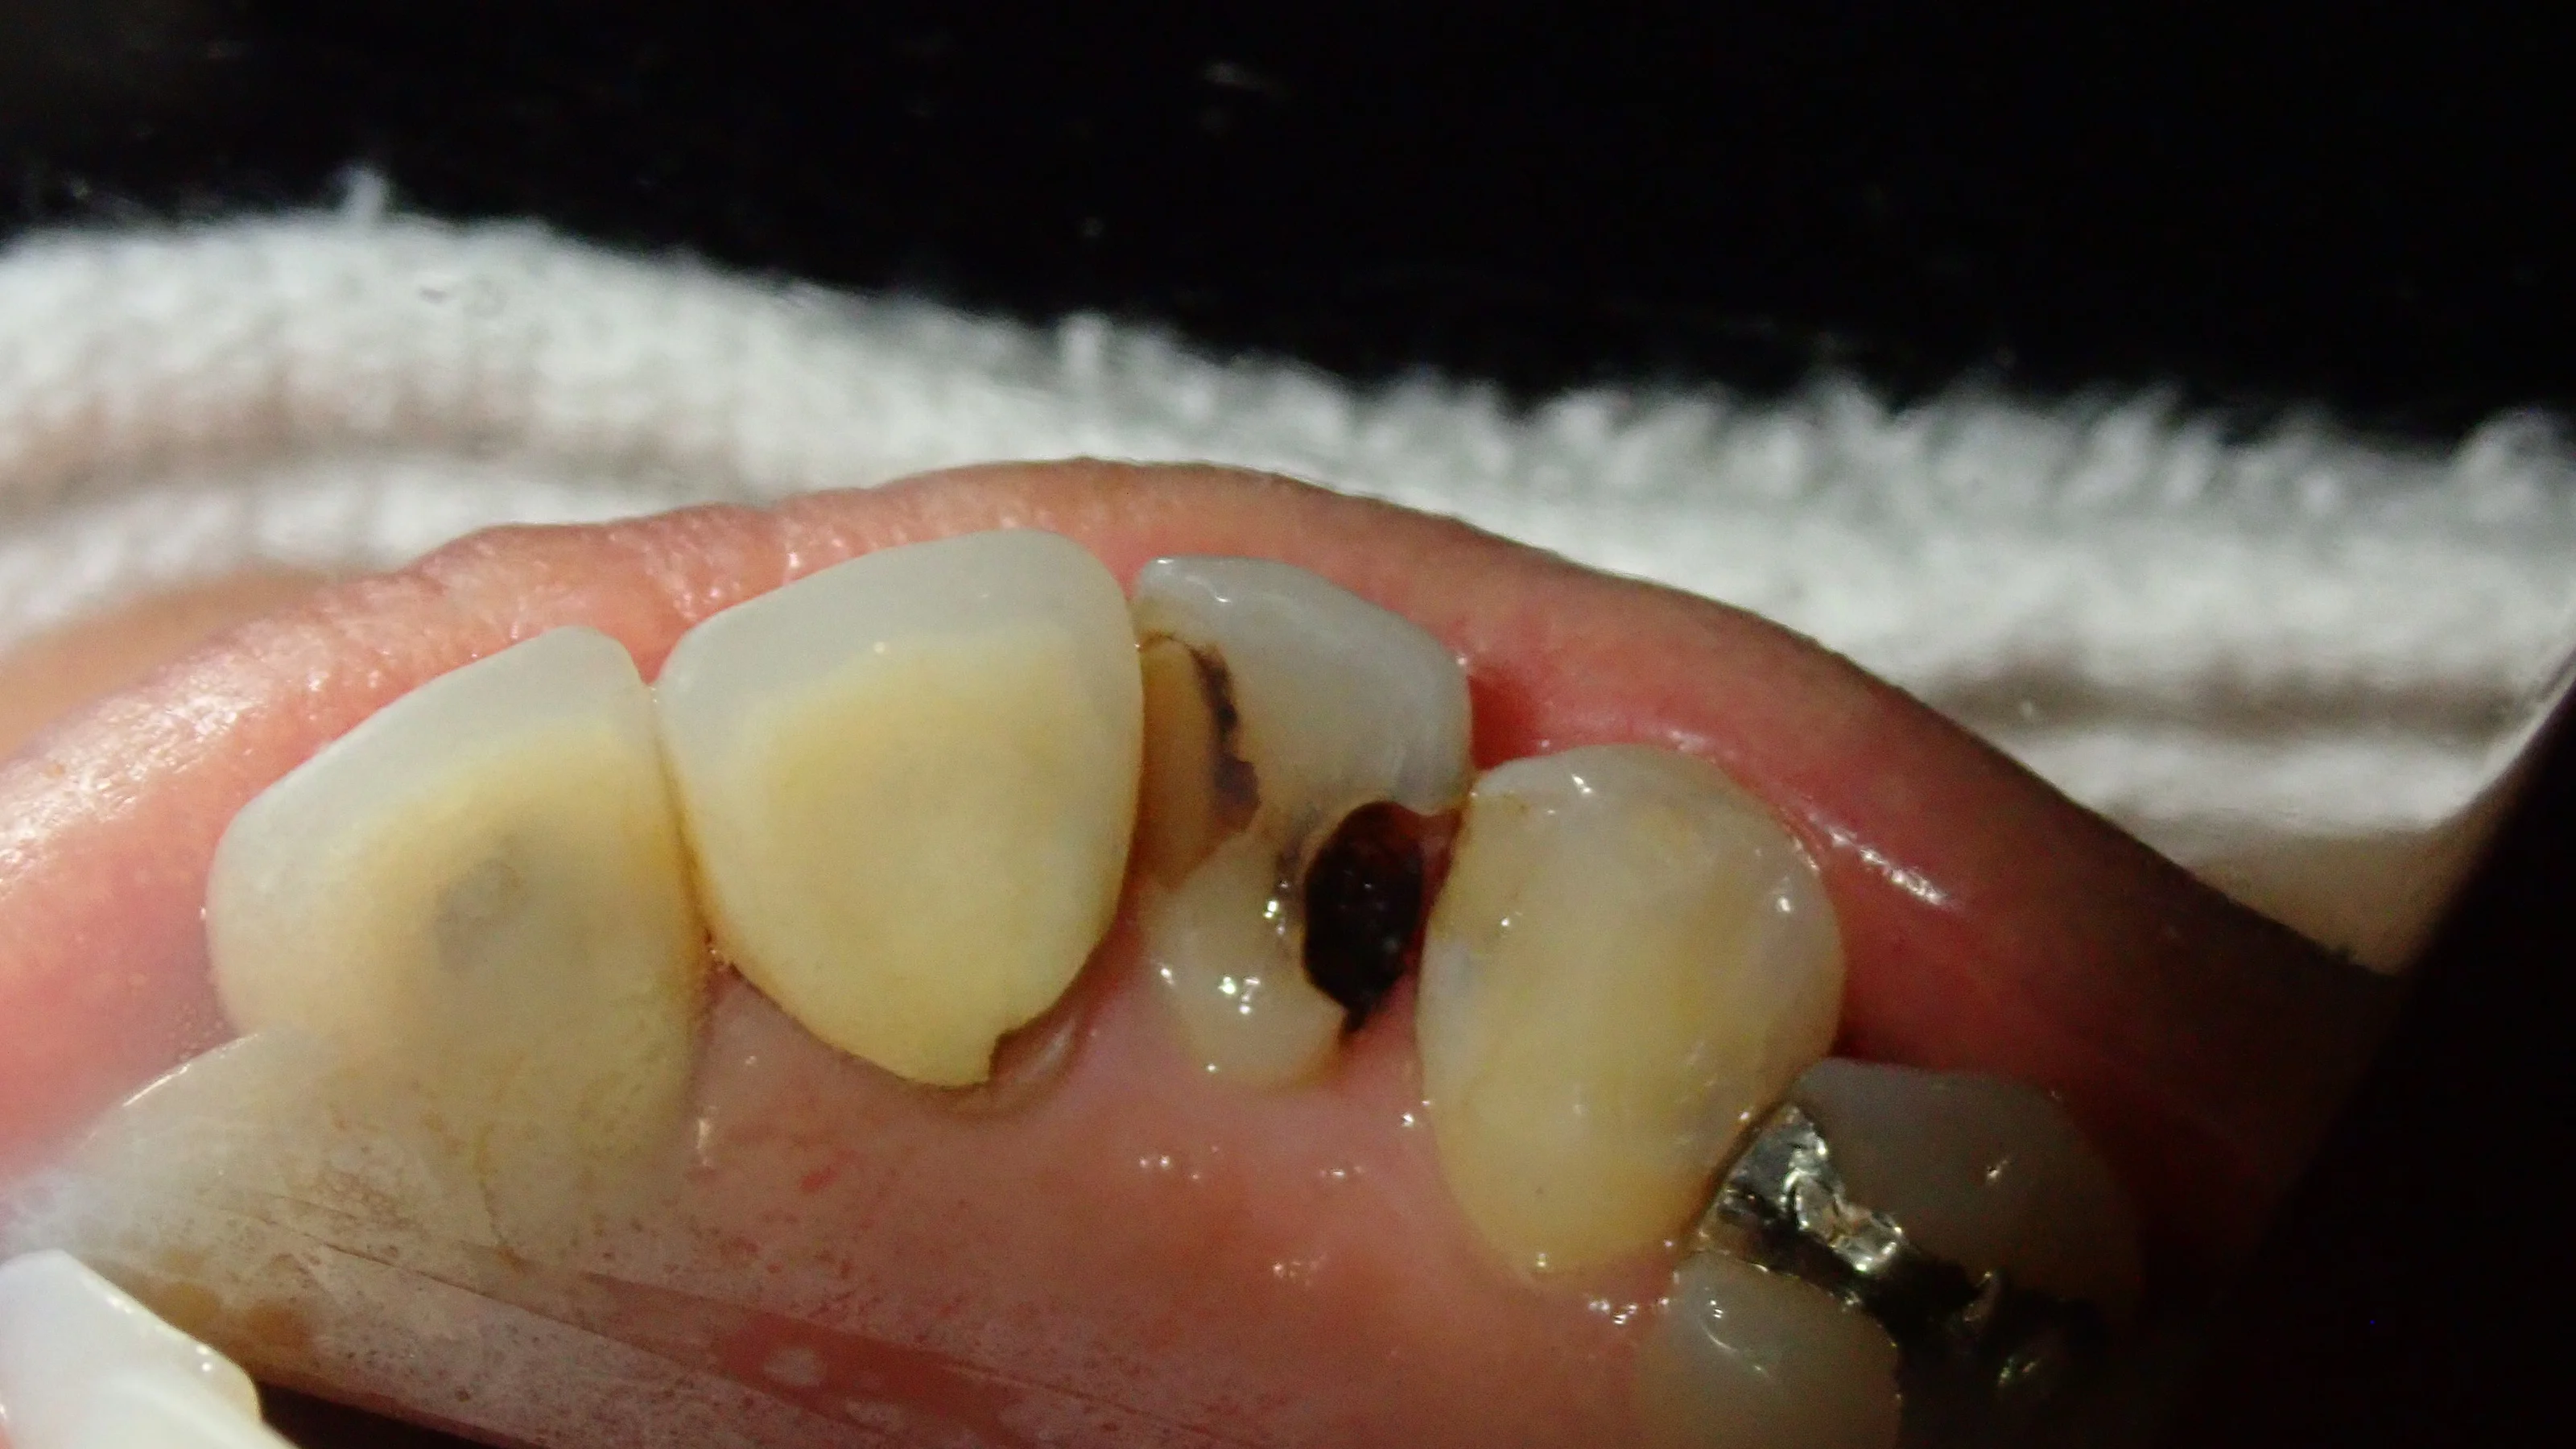

裏側から見るとこんな状態になってしまっていました。

前後の歯の間から虫歯が入り込み、歯の中央で虫歯が繋がっている状態となっています。

歯科医師によってはいきなり抜髄処置に入ってもおかしくはないほどの虫歯です。

殆どの歯医者さんではこのサイズの虫歯は、恐らく被せ物以外の選択肢を出されないかと思います。

この状態であれば、私も被せ物を勧めさせていただくことが多いですね。

ただ、今回の場合は

・そもそも下の歯と噛み合っていない

・初めて治療をする歯だったので、むやみやたらと歯を削られていなかった

・そして思った以上に歯を温存できた

という点からダイレクトボンディングによる治療が可能と判断し、本人にも説明した上で処置に入らせて頂きました。